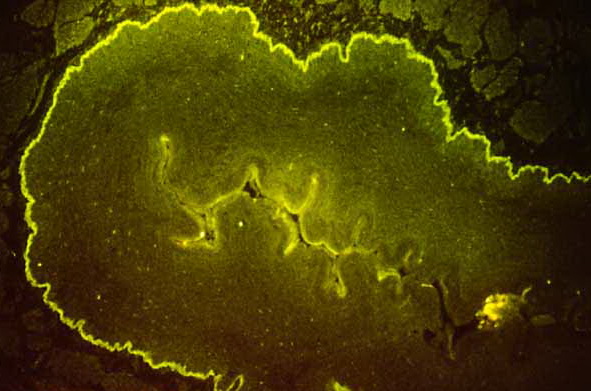

IF Testing. DIF testing of perilesional skin has shown linear C3 deposition  at the dermal-epidermal junction in virtually 100% of cases and IgG in 65% to 95%. IIF studies reveal circulating anti­basement membrane zone IgG antibodies in 70% to 80%. Similarly deposited IgA and IgM are observed in about 25% of cases. No correlation exists between the antibody titer and the clinical severity of the disease. The IgG is located within the lamina lucida, where it appears to be bound specifically to the hemidesmosomes.

Salt-split skin IF studies are an important diagnostic tool. The technique was first developed in 1984, in which normal human skin was used as a substrate and patient serum as a test (indirect salt-split skin technique) (91). Incubation of normal or patient skin in 1 mol/L NaCI results in a split of the epidermis in the lamina lucida. Pemphigoid antibodies bind solely to the lower aspect of the basal keratinocytes (the blister roof) in 80% of cases; in about 20% of cases, the antibodies bind to both the lower basal keratinocytes (the roof) and the superior aspect of the dermis (the blister floor) (T. It must be made clear that the antigenic specificity of the IgG binding to the base or roof is unknown. The IgG cannot be said to be directly against BPAg 1, 2, or other antigen. As time goes on, it is likely that it will be found that a number of cases have different antigenic specificity and should be labeled as different diseases.